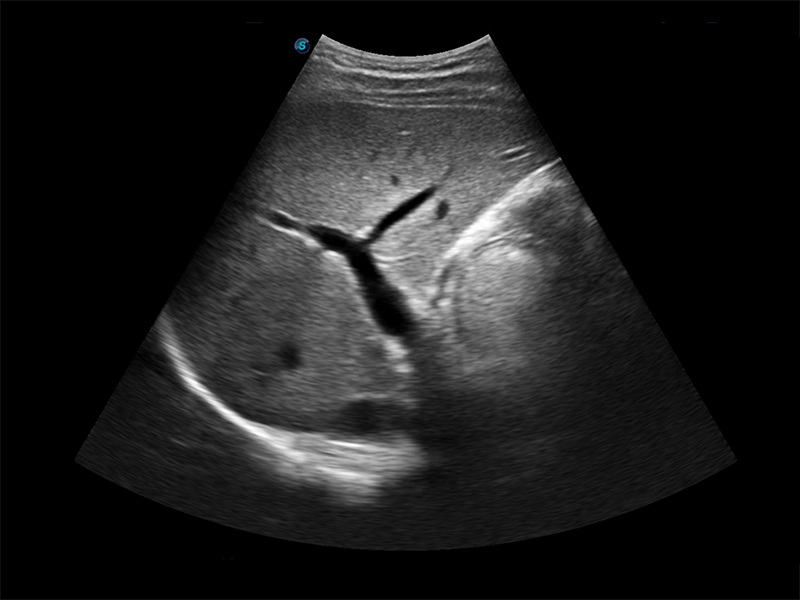

Aparat E1 to nowy model przenośnego, czarno-białego ultrasonografu, który wyposażono w bogaty pakiet funkcji wyróżniających go na tle konkurencyjnych modeli ultrasonografów klasy podstawowej. Aparat ten zapewnia użytkownikom nie tylko satysfakcjonującą jakość obrazów, lecz również usprawniony przebieg pracy.